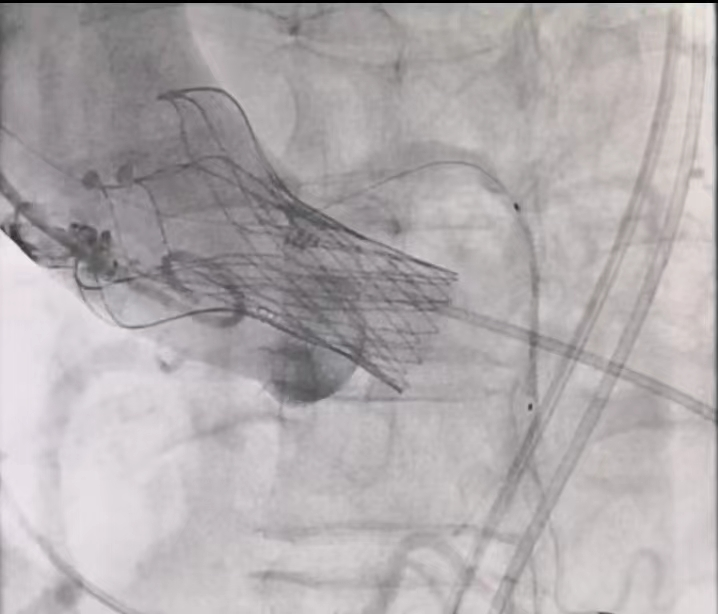

(开窗支架示意图)

1,人工瓣膜释放后左冠位造影提示左冠堵塞风险高

2,保留瓣架外预埋通路,通过瓣架网眼再建通路成功